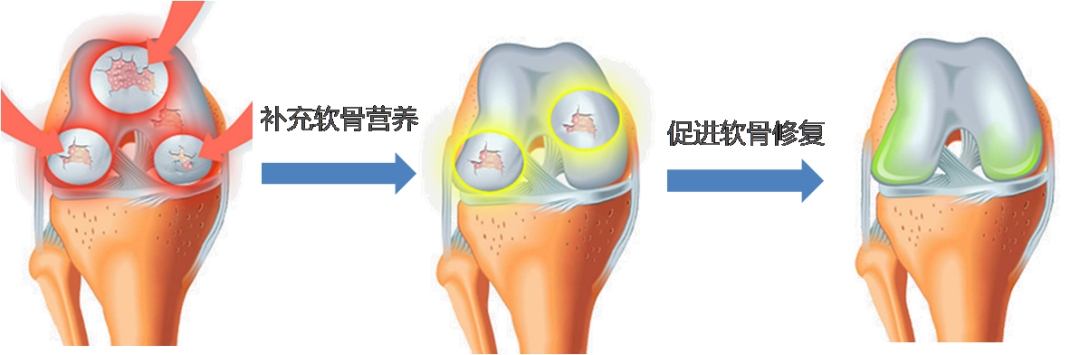

氨糖

根据中国老教授协会骨质疏松与骨关节病专家委员会主任、北京积水潭医院骨科研究所研究院薛延教授研究,骨关节病和人体内氨糖的含量有关。氨糖的全称是D-氨基葡萄糖,是一种单糖,它能合成人体中关节软骨基质的原料。正常情况下,软骨细胞利用葡萄糖合成氨基葡萄糖,进一步合成蛋白多糖。骨关节炎发生时,软骨细胞得到的葡萄糖减少。此时补充氨基葡萄糖,合成蛋白多糖,保护与修补软骨基质和恢复受损的软骨细胞。使用氨糖补充剂,对骨关节炎可起到润滑、消炎、镇痛、修复以及提高关节功能和机体免疫力的作用。

据统计,30岁过后,氨糖在人体内的含量逐渐降低并不再生成,45岁以后氨糖含量仅相当于18岁的18%,70岁以后几乎消耗殆尽。薛延教授通过对406例中老年骨关节炎患者临床观察发现,及时补充氨糖5个月以上,对骨关节炎的有效改善高达97%,而仅仅补充两三个月,有效改善率也高达83%。

硫酸软骨素

硫酸软骨素(CS)是共价连接在蛋白质上形成蛋白聚糖的一类糖胺聚糖,是构成关节软骨蛋白多糖的成分之一。它具有明显的亲软骨性,吸收后可优先进入软骨组织,增加关节内的滑液量,提供“垫衬”作用,增强关节减震能力。在医学上主要的应用途径是作为治疗关节疾病的药品,与氨基葡萄糖配合使用,具有止痛、促进软骨再生的功效,可以改善骨关节问题。